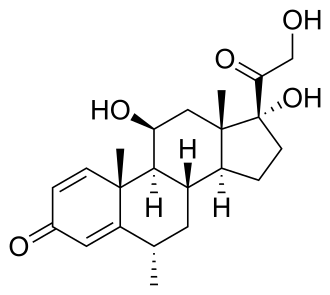

Long term neurologic deficits are the cumulative effects of acute attacks, emphasizing the importance of acute treatment.[1] Traditionally, attacks have been treated with short courses (3–5 days) of high dosage intravenous corticosteroids, such as methylprednisolone IV (Solu-Medrol).[58] Early initiation of treatment with steroids has been shown to improve vision-related outcomes after acute attacks.[1][59] However, there is no high-level evidence for steroids affecting long-term outcomes; this treatment strategy was borrowed from that for similar diseases (idiopathic optic neuritis and multiple sclerosis).[59][58]

Off-label treatments

| azathioprine (Imuran, Azasan) | Inhibits purine metabolism | First reported effective in 1998 and was mainstay of treatment 10+ years thereafter. Sometimes combined with steroids due to months-long onset of action.[1] |

| mycophenolate mofetil (CellCept) | Inhibits purine metabolism | Has partially replaced azathioprine due to proposed better efficacy and tolerability. Sometimes combined with steroids due to months-long onset of action.[1] |

| corticosteroid | [66] | |

| mitoxantrone | DNA synthesis/repair inhibitor | |

| methotrexate | Inhibits folate metabolism | |

| cyclophosphamide | DNA crosslinker | |

| rituximab (Rituxan) | antibody against CD20 – B cell depletion[67] | The most commonly used treatment for NMOSD today.[68] |

| intravenous immunoglobulin (IVIG) | ||

| hematopoietic stem cell transplantation (HSCT) | can be used in severe cases of NMO. Available data suggests that this procedure can reduce inflammatory activity in the short term, but a clear majority of the patients will relapse within 5 years.[69] |

It is important to note that certain immunosuppressants used to treat MS—such as interferon-β, fingolimod, natalizumab, and alemtuzumab—worsen NMO disease progression and should not be used to treat NMO.[70]